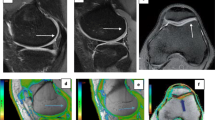

a Sagittal fat-suppressed proton density-weighted shows full-thickness defects of articular cartilage of medial tibiofemoral condyle and exposed subchondral bone (blue arrow). b and c Corresponding T2 map shows elevated cartilage T2 relaxation time (ROI). [b: 0 ms ≤ T2 ≤ 39 ms; c: T2 = 74 ms (>50 ms)]

a Sagittal fat-suppressed proton density-weighted image shows a preserved signal intensity of the articular cartilage of the anterior aspect of medial femoral condyle with uniform cartilage thickness (blue arrow). b and c The corresponding T2 map shows increased cartilage T2 relaxation time (ROI). b: 0 ms ≤ T2 ≤ 39 ms; c: T2 = 63 ms)

a Sagittal fat-suppressed proton density-weighted image shows a preserved signal intensity of the articular cartilage of the posterior aspect of the medial femoral condyle with uniform cartilage thickness (blue arrow). b and c Corresponding sagittal T2 map shows a region of increased T2 relaxation time [false positive] (ROI). b: 0 ms ≤ T2 ≤ 39 ms; c: T2 = 66 ms)

a Sagittal fat-suppressed proton density-weighted shows preserved signal intensity of the cartilage covering the medial femoral articular cartilage with uniform cartilage thickness (blue arrow). b and c Corresponding T2 map shows normal cartilage T2 relaxation time (ROI). b: 0 ms ≤ T2 ≤ 39 ms; c: T2 ≤ 40 ms)